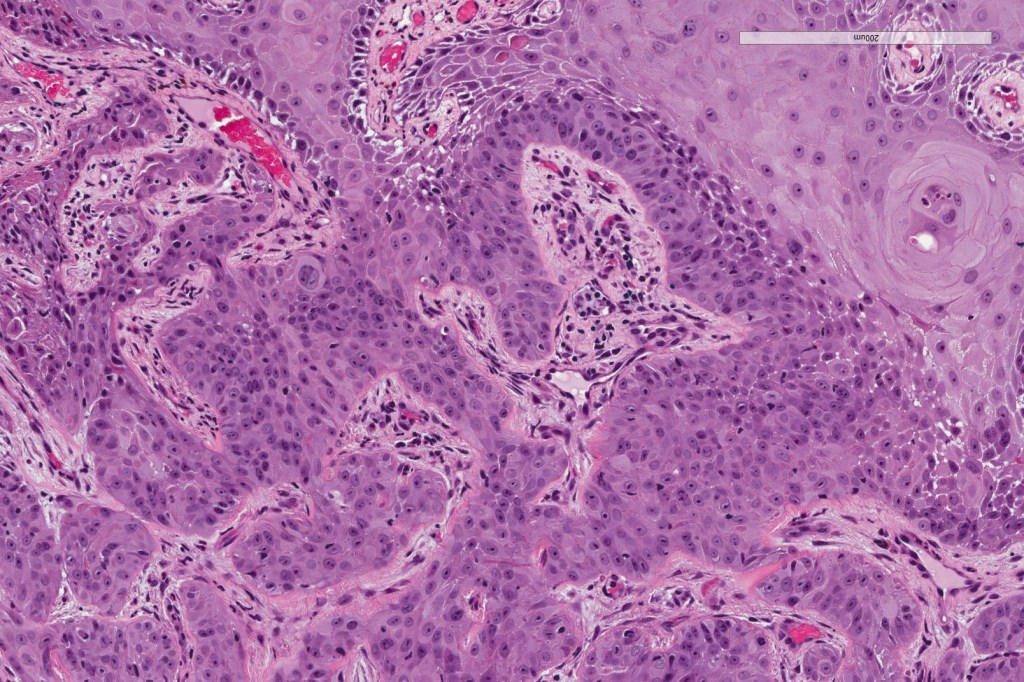

Histological features

•Broad anastomosing epithelial trabeculae

•Ducal differentiation invariably present

•Intracytoplasmic lumina

•Squamous differentiation